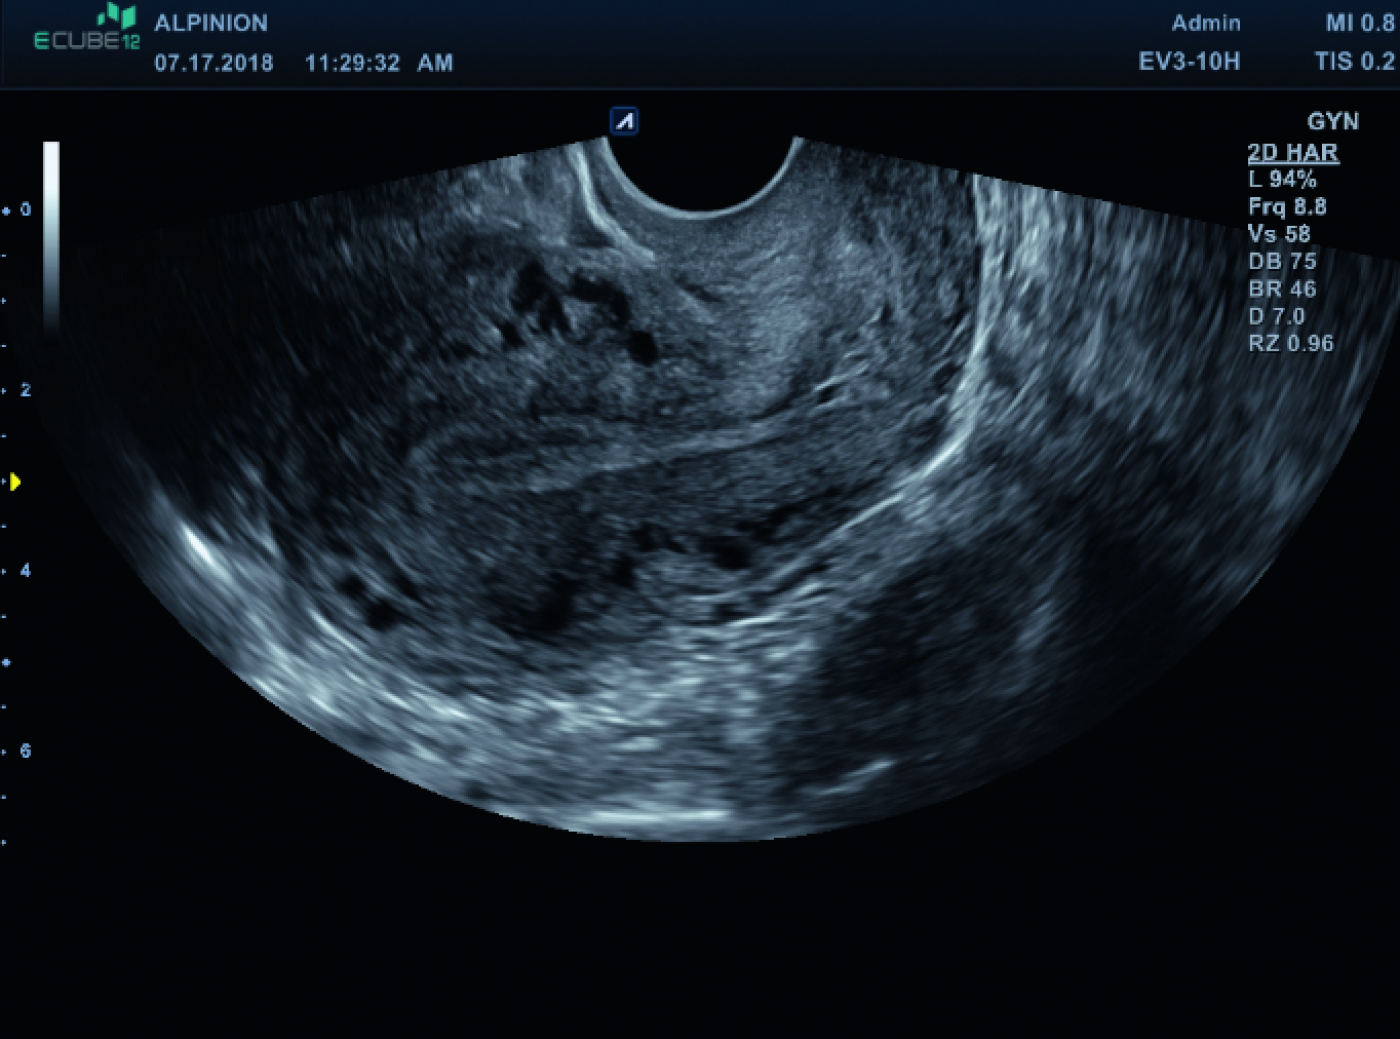

Gynäkologische

Ultraschalldiagnostik

mit Präzision & Komfort

Moderne Frauenheilkunde stellt höchste Anforderungen an Bildqualität, Bedienkomfort und Vielseitigkeit. ALPINION unterstützt Gynäkologinnen und Gynäkologen mit leistungsstarker Ultraschalltechnologie, die sowohl im Praxisalltag als auch im klinischen Umfeld überzeugt. Unsere Systeme liefern hochauflösende Bilder bei transabdominaler und transvaginaler Sonografie – für eine sichere, schnelle und präzise Diagnostik in allen Phasen der Frauengesundheit.

• Speziell entwickelte Endokavitärschallköpfe für höchsten Patientinnenkomfort